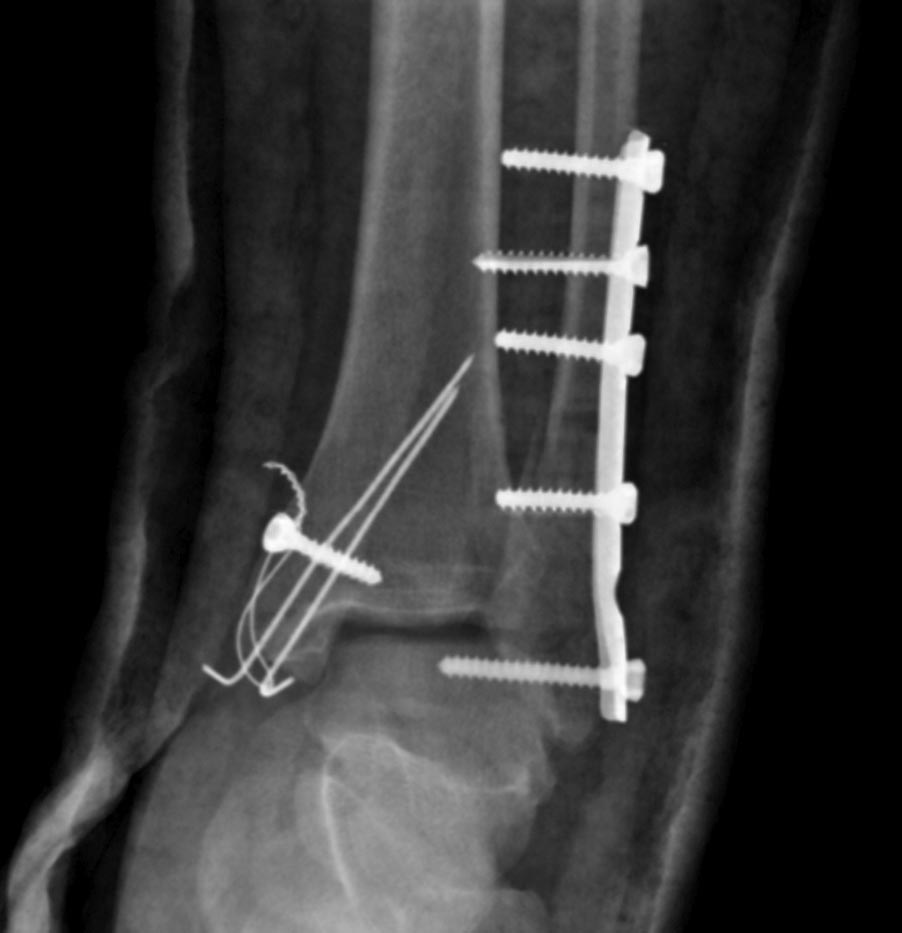

Здравствуйте. Операция 2 дня назад по дежурству, объем движений в

голеностопном суставе в полном объеме. Пациенту 35 лет. Ограничиться

заменой длинных винтов либо делать реостеосинтез малоберцовой кости?